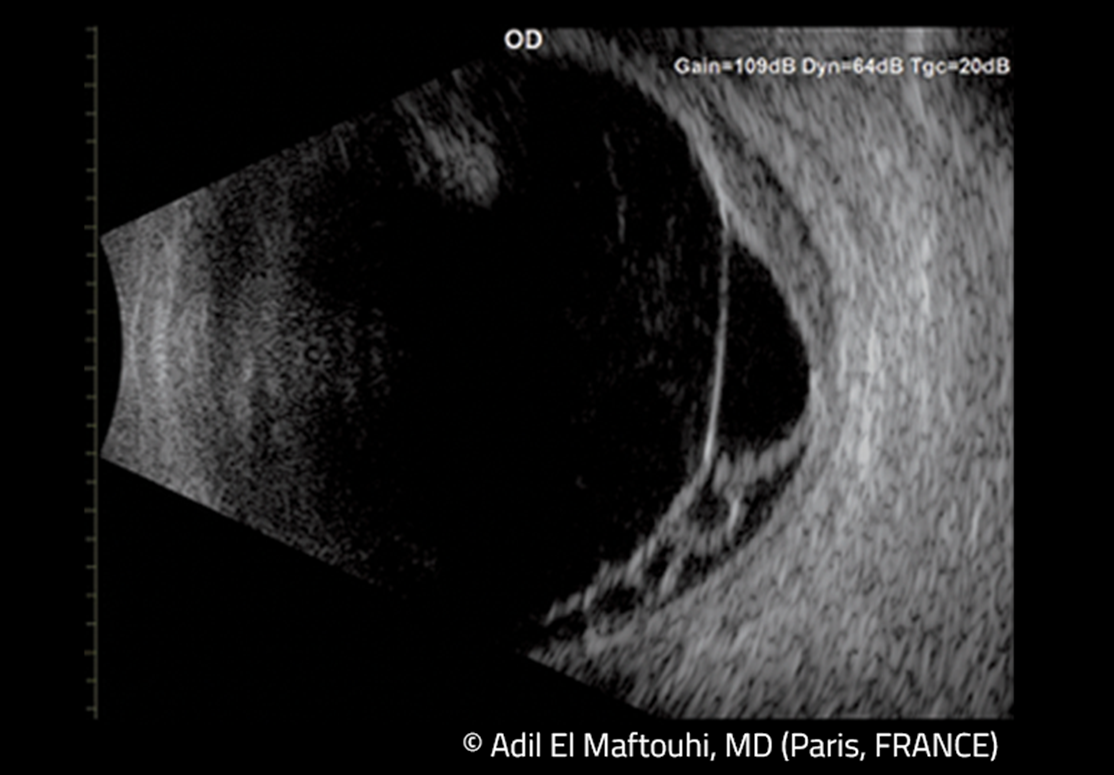

Nový ultrazvukový prístroj Compact Touch ponúka režimy A/B a pachymetriu. Ťaží z novej generácie 15MHz sondy so zvýšeným rozlíšením až o 30 %. Vďaka malým rozmerom sa zmestí do akéhokoľvek pracovného prostredia, dokonca aj do tých najmenších vyšetrovacích miestností. Po pripojení ľahko prepojí namerané údaje s vašimi sieťami DICOM, EMR alebo Wifi.

- nová 15 MHz sonda prináša výnimočnú kvalitu obrazu pre lepšiu a rýchlejšiu diagnostiku,

- kombinuje 3 v jednom 15 MHz B-scan, voliteľná sonda – pachymetria, A-scan.